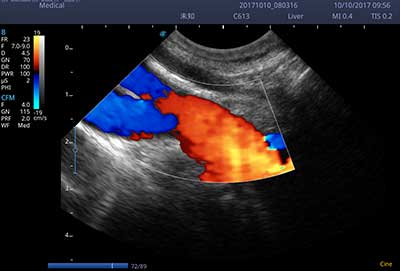

E3便携式彩色多普勒超声诊断系统拥有专业超声技术平台、高度集成化的硬件模块和结构设计、简便的操作流程、支持三探头接口全激活,兼顾了优质图像、轻便机身以及台便两用的临床使用需求。无论在常规超声科门诊检查,还是在急诊、麻醉、ICU、户外等各种应用场景。都能给您带来流程的操作体验。

• SR Flow 高分辨率血流